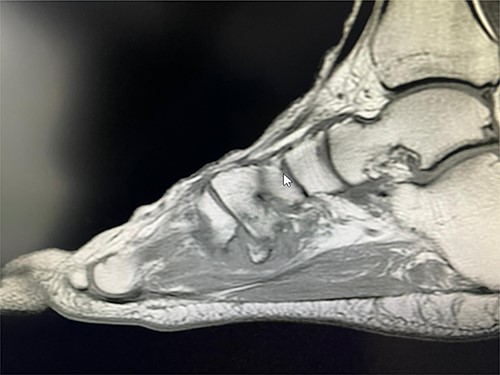

Based on this examination, the initial impression was tendinosis of the flexor hallucis longus. To confirm this diagnosis and rule out any other bony injury, a magnetic resonance imaging scan was requested of the right foot and ankle. Imaging revealed an avulsion of peroneus longus tendon at base of first metatarsal with a possible non-union as well (Figs 1–3).

Coronal T2 view showing the non-union of the first metatarsal avulsion fracture.